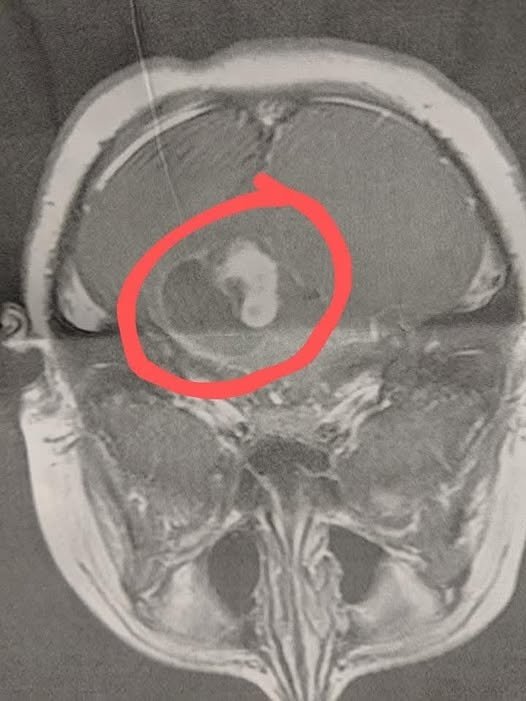

The MRI revealed a large brain tumor with fluid around it. Within hours, we were at Duke Hospital, preparing for emergency brain surgery. The operation lasted eight long hours. The surgeons were able to remove about 90% of the tumor, but the remaining 10% was wrapped around his brain stem and too dangerous to remove.

Six weeks later, we returned for a follow-up MRI to see how he was healing. That’s when we got the devastating news — the tumor had already grown back. Without hesitation, my son began chemotherapy, starting an intense year-long battle.